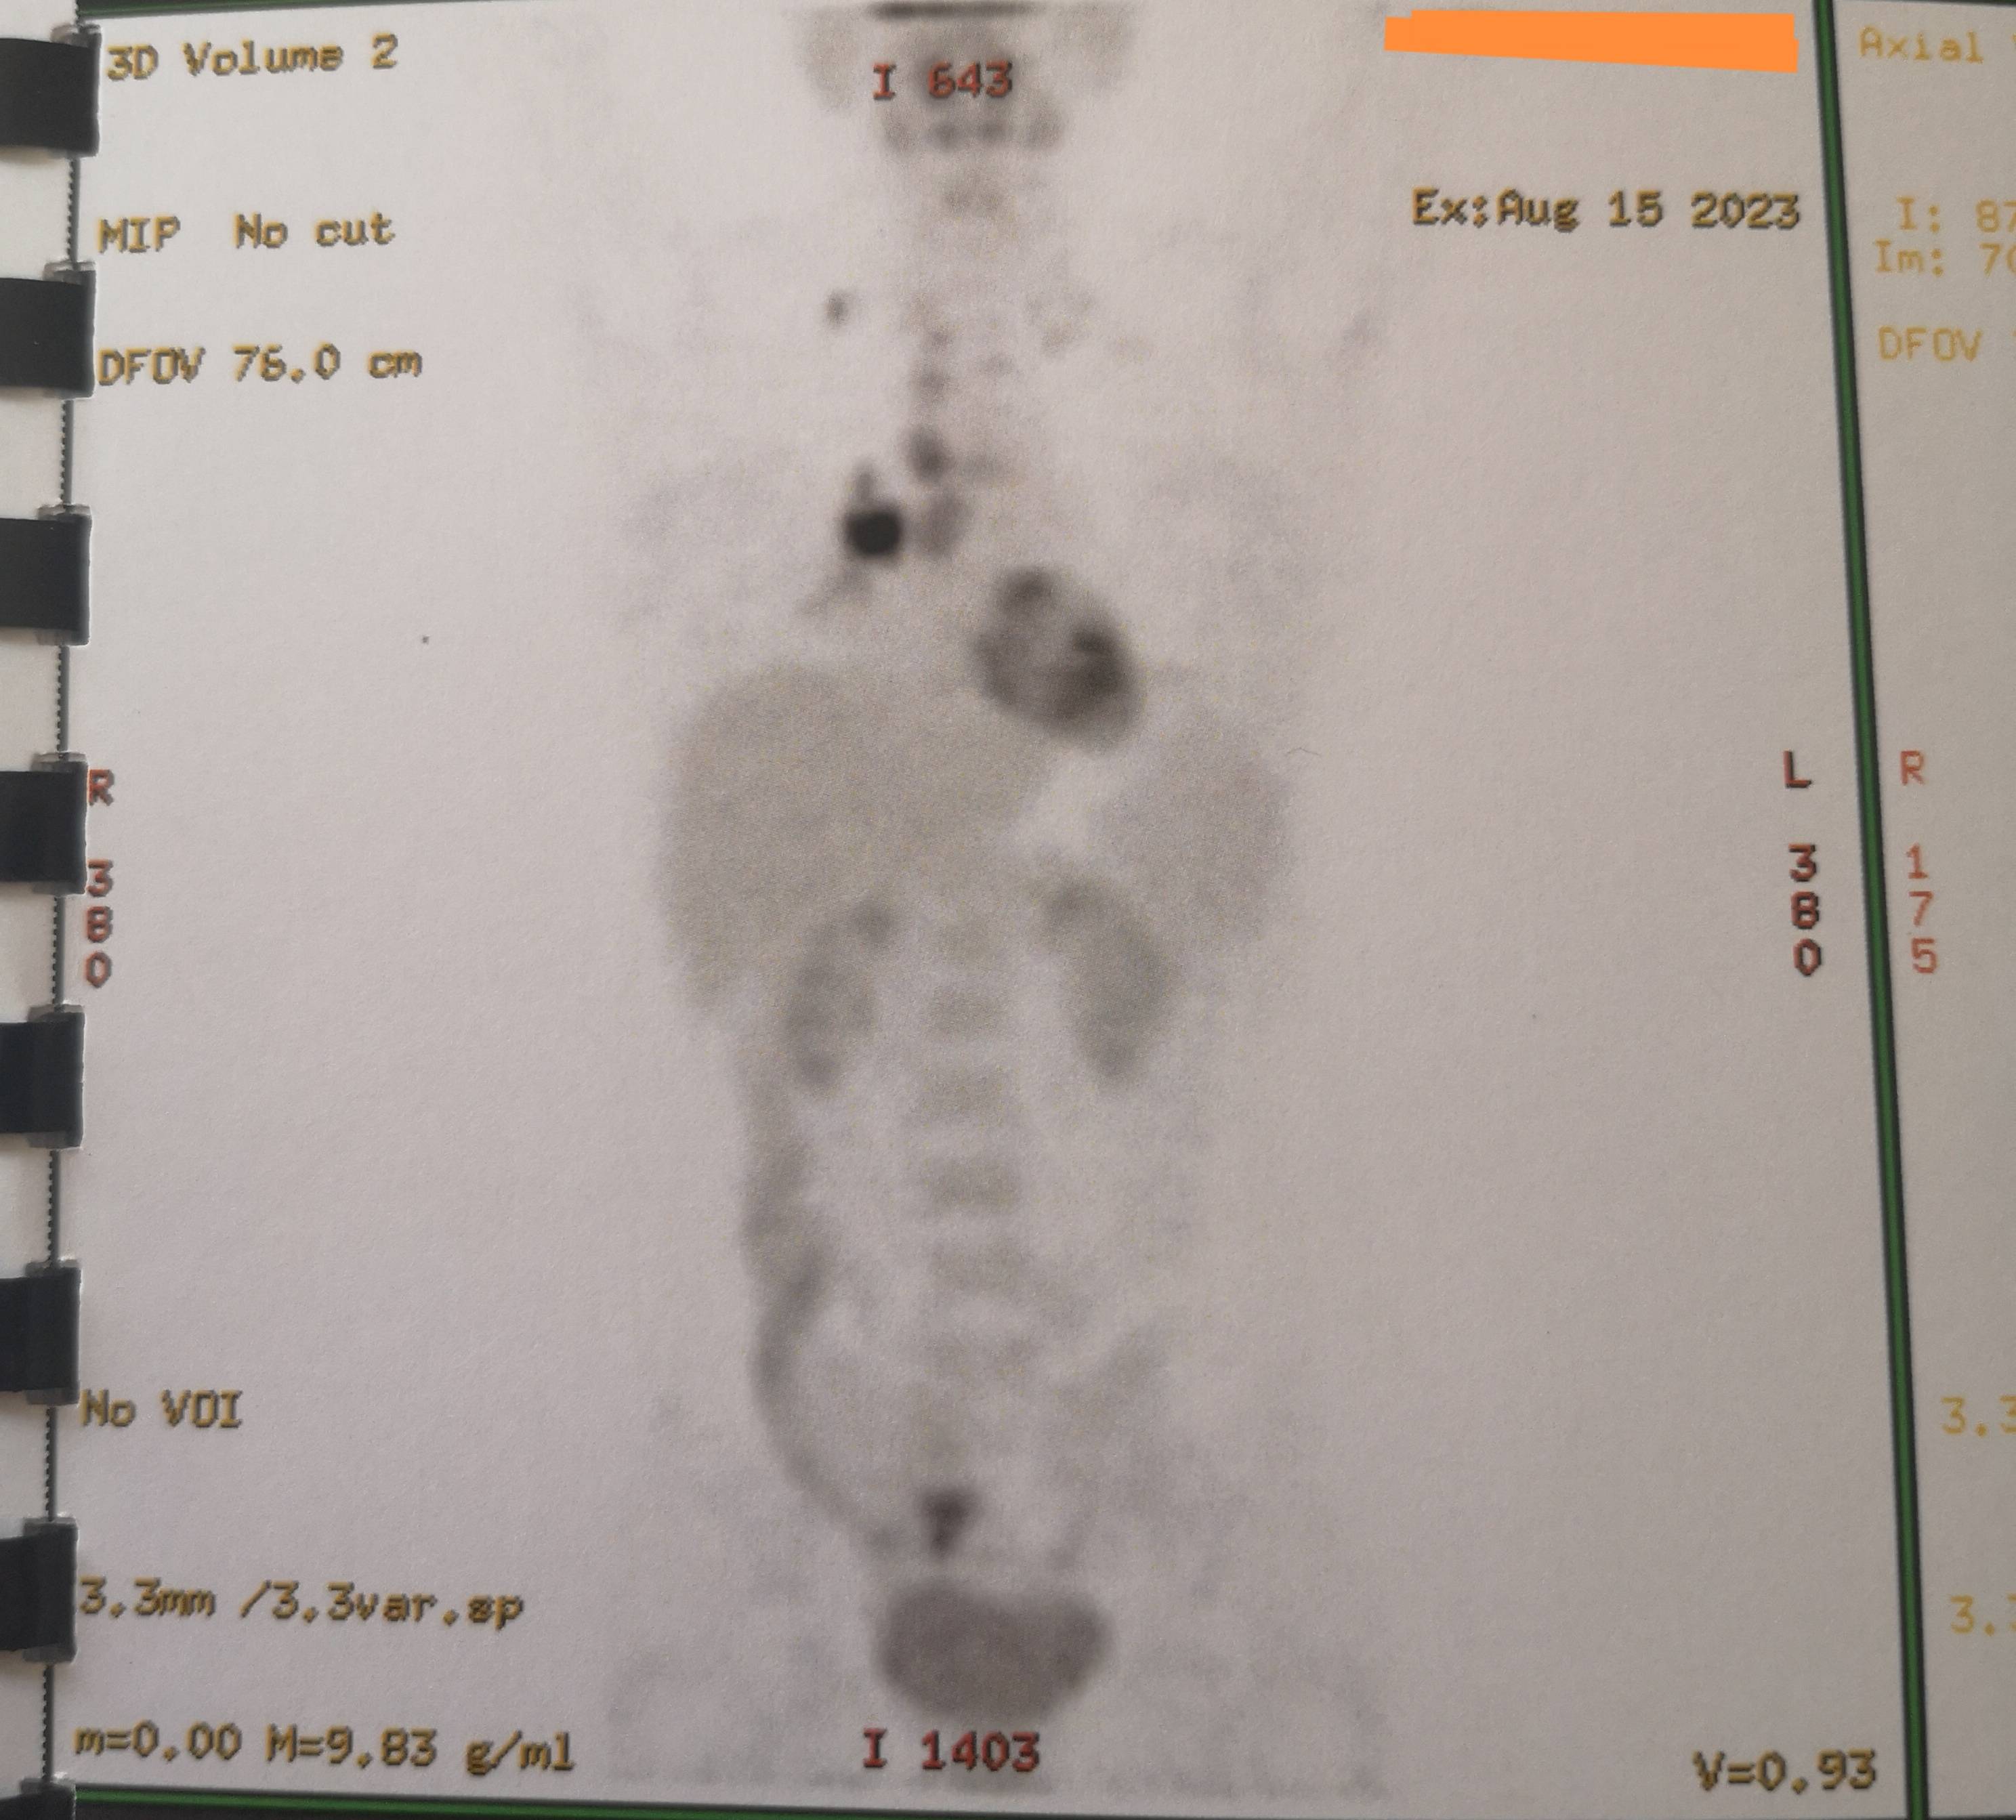

左侧锁骨淋巴的结节数据基本没有变化,昨天朋友提醒我,找下最早的PET/CT报告。

左侧第一次数据0.9×1.8数据比右侧数据还大,可是PETCT报告好像没有显示左侧的暗影区。